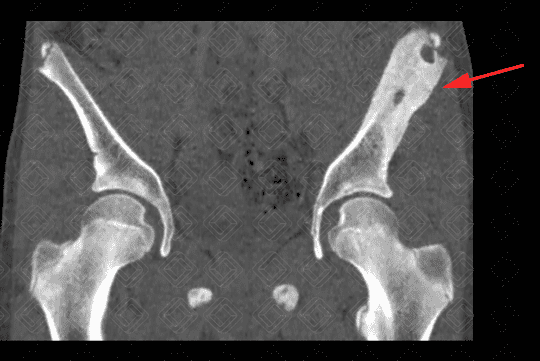

Texto alternativo para a imagem Figuras 1, 2 e 3. Créditos: Dra. Elazir Mota - Rio de Janeiro/RJ

Descrição das figuras 1, 2 e 3: Tomografia computadorizada de bacia, após a administração do contraste venoso. Paciente do sexo masculino, 13 anos, evidenciando extensa área de esclerose na asa do ilíaco esquerdo, com áreas líticas de permeio (setas vermelhas). Na janela de partes moles, observa-se aumento de partes moles e coleção adjacente à lesão óssea descrita (asterisco).